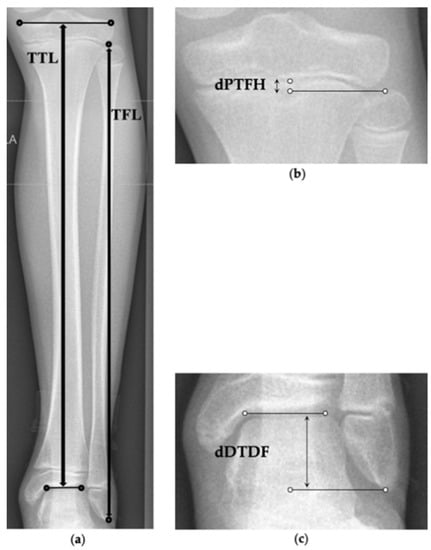

2.5. Radiographic Analysis

- Frommer, A.; Niemann, M.; Gosheger, G.; Toporowski, G.; Laufer, A.; Eveslage, M.; Broking, J.N.; Rodl, R.; Vogt, B. A new standard radiographic reference for proximal fibular height in children. Acta Orthop. 2020, 1–6. [Google Scholar] [CrossRef] [PubMed]

- Panchbhavi, V.K.; Gurbani, B.N.; Mason, C.B.; Fischer, W. Radiographic assessment of fibular length variance: The case for “fibula minus”. J. Foot Ankle Surg. 2018, 57, 91–94. [Google Scholar] [CrossRef]